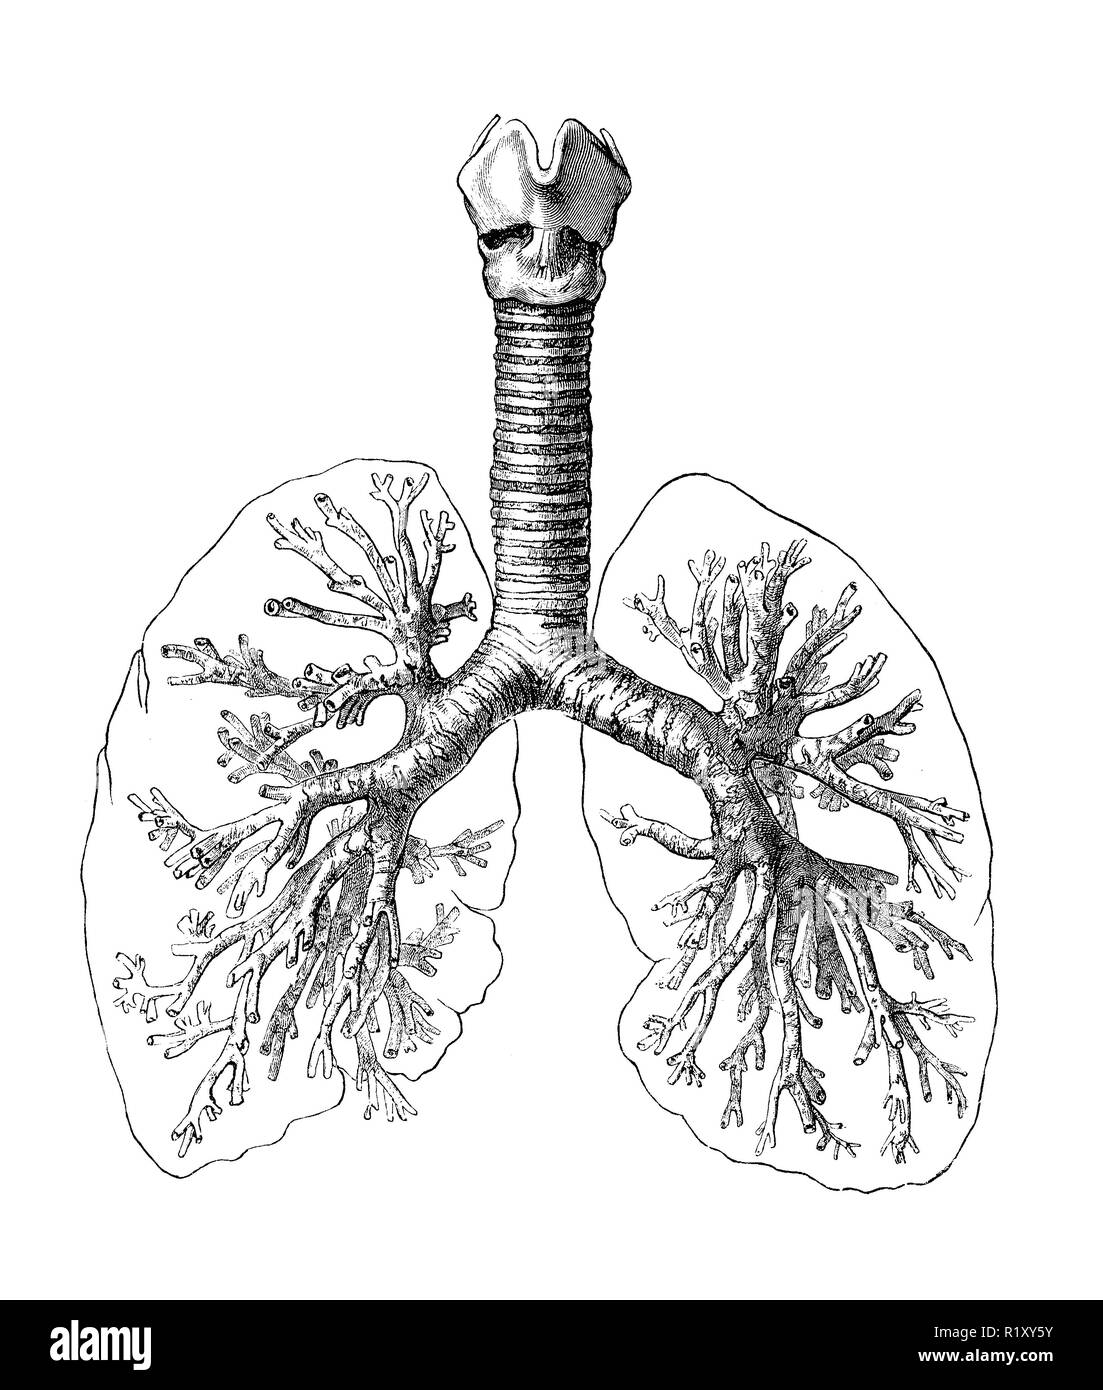

Vintage illustration de l'anatomie, système respiratoire humain : les bronches, la trachée et les poumons Banque D'Imageshttps://www.alamyimages.fr/image-license-details/?v=1https://www.alamyimages.fr/vintage-illustration-de-l-anatomie-systeme-respiratoire-humain-les-bronches-la-trachee-et-les-poumons-image224941527.html

Vintage illustration de l'anatomie, système respiratoire humain : les bronches, la trachée et les poumons Banque D'Imageshttps://www.alamyimages.fr/image-license-details/?v=1https://www.alamyimages.fr/vintage-illustration-de-l-anatomie-systeme-respiratoire-humain-les-bronches-la-trachee-et-les-poumons-image224941527.htmlRFR1XY5Y–Vintage illustration de l'anatomie, système respiratoire humain : les bronches, la trachée et les poumons